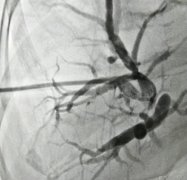

刘淑华,今年71岁,2017年4月中旬因突发大面积脑梗死并引发一系列并发症,先后在市人民医院和杭州邵逸夫医院就诊。在邵逸夫医院她的家属了解到早期康复治疗的重要性,经人介绍,得知海宁皮城康复医院已经开业,遂于5月初转入皮城康复医院,并拟“偏瘫”收治入院。

入院时,刘淑华情况较差,右侧肢体活动不利伴言语含糊、神志欠清、大小便失禁等症状,由家人平板车推入皮城康复医院综合病区。通过康复医师和治疗师的诊断和系统评估后,为其制定了一套完整的治疗方案。